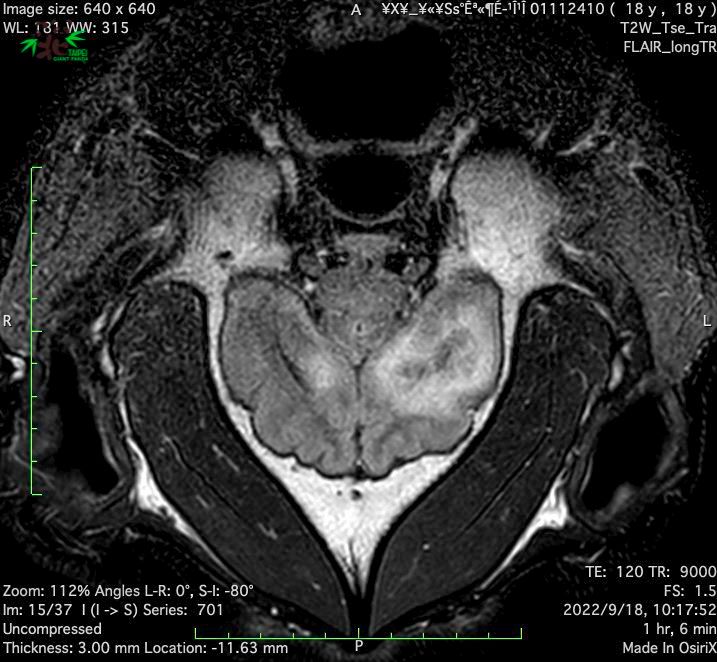

经医师判断,认为团团必须接受脑部MRI(磁振造影) 精密的检查来厘清癫痫发生的原因,特别安排「团团」9月18日到台大附设动物医院接受相关检查。

MRI影像显示「团团」左大脑半球有局部液化坏死病变,右大脑半球亦可见类似病变,此病变可能是造成团团癫痫发作的原因。为进一步厘清脑部病变的可能肇因,兽医师为「团团」采取脑脊髓液进行后续的分析化验,也同时完成整体生理检查。

MRI影像显示「团团」左大脑半球有局部液化坏死病变,右大脑半球亦可见类似病变。翻摄自动物园官网